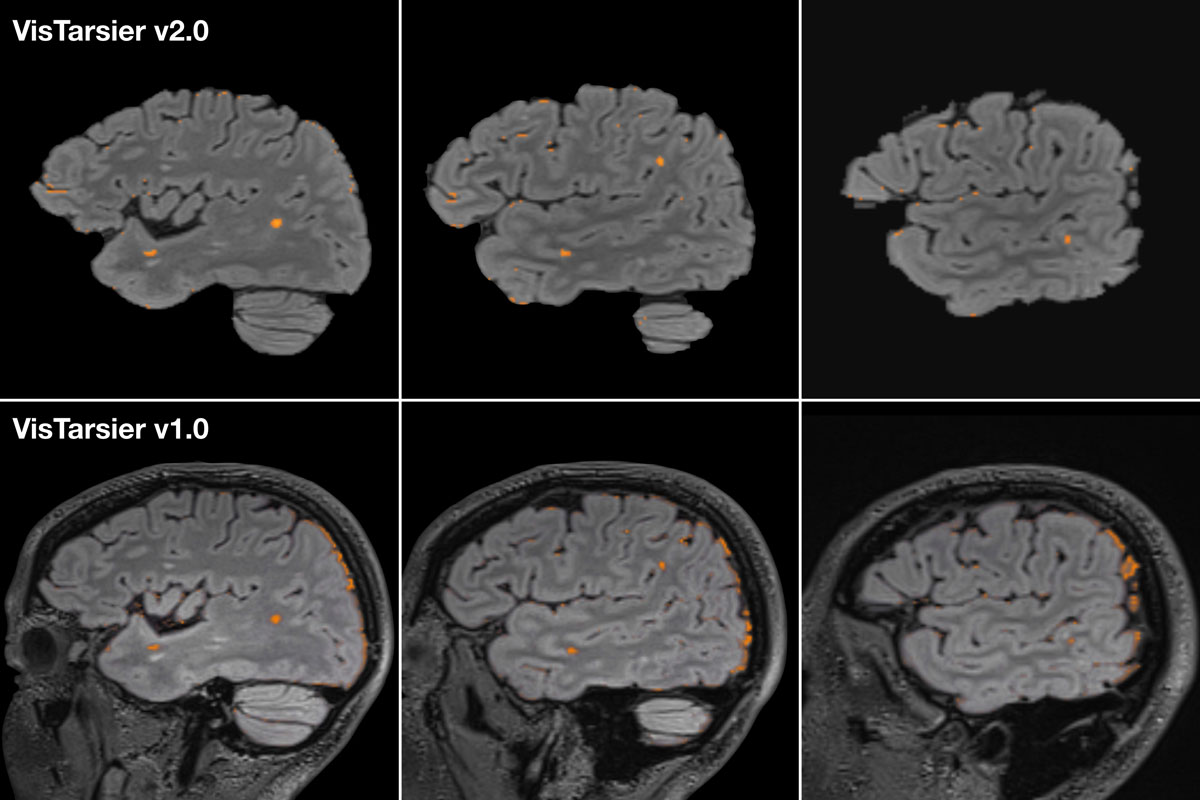

Figure 3: The following images demonstrate VT1 vs VT2 on the same slice of the same patient showing improved lesion visualisation and decreased non-pathological noise.

The original (validated) version of the software (VT1) has undergone additional development and the current version (VT2) includes a number of improvements:

- bias field correction

- reduction of non-parenchymal signal change

- improved skull stripping and masking